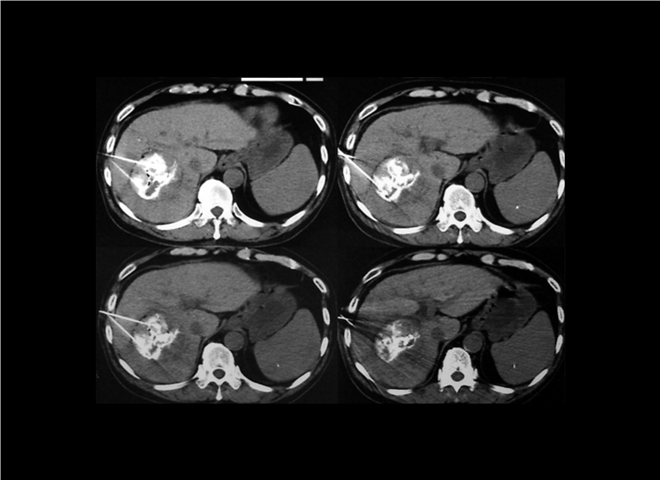

13_CT增强扫描